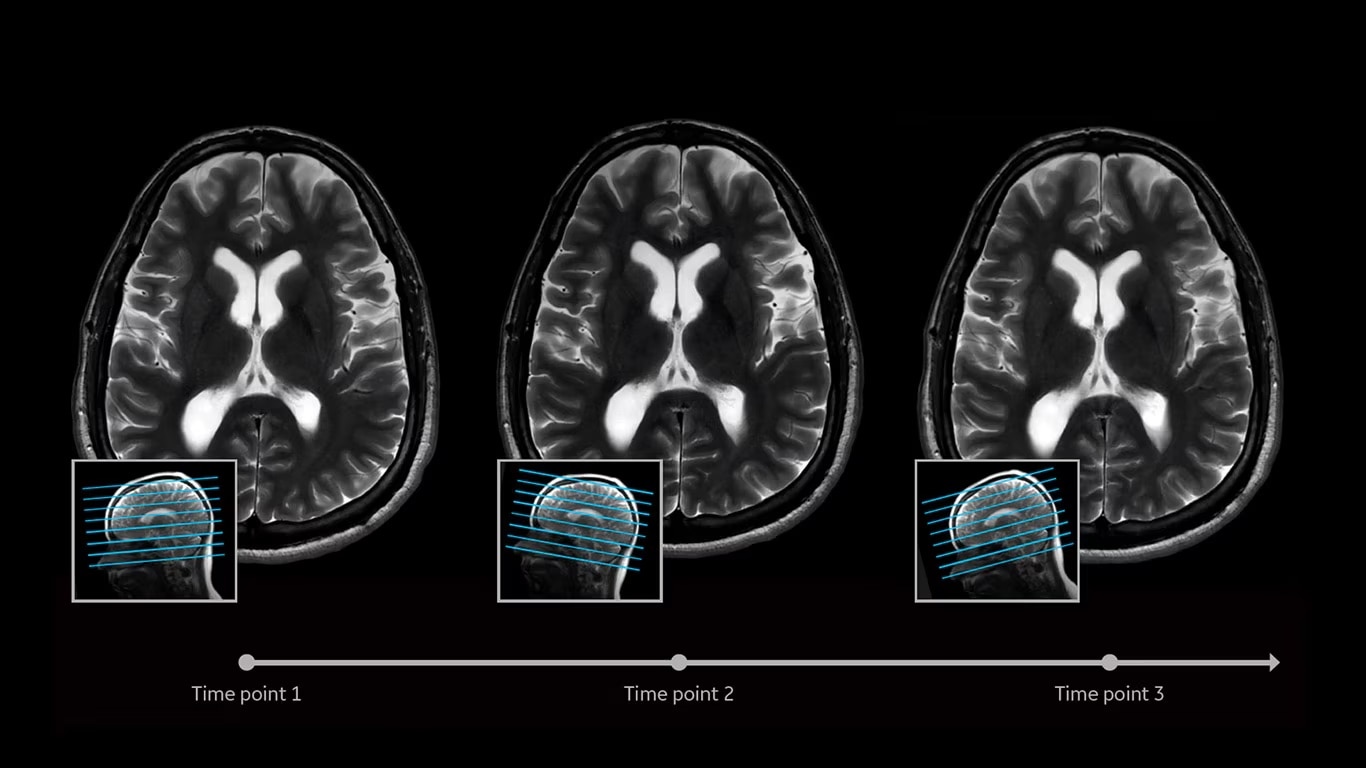

Eliminate the sources of variation by letting processes flow. AIR x uses deep-learning algorithms created from a database of 10's of thousands of images to automatically detect patient anatomy and prescribe MRI slices for routine and challenging neurological and knee exams, delivering consistent and quantifiable results. The automated workflow creates efficiency and reproduces steps used in planning to ensure exam consistency for same patient follow-up.

AIR x automatically detects patient anatomy and prescribes MRI slices for routine and challenging neurological and knee exams, delivering consistent and quantifiable results.

Deliver consistent MRI slice placements across multiple clinical time points, with a deep-learning algorithm that provides efficiency and time savings.